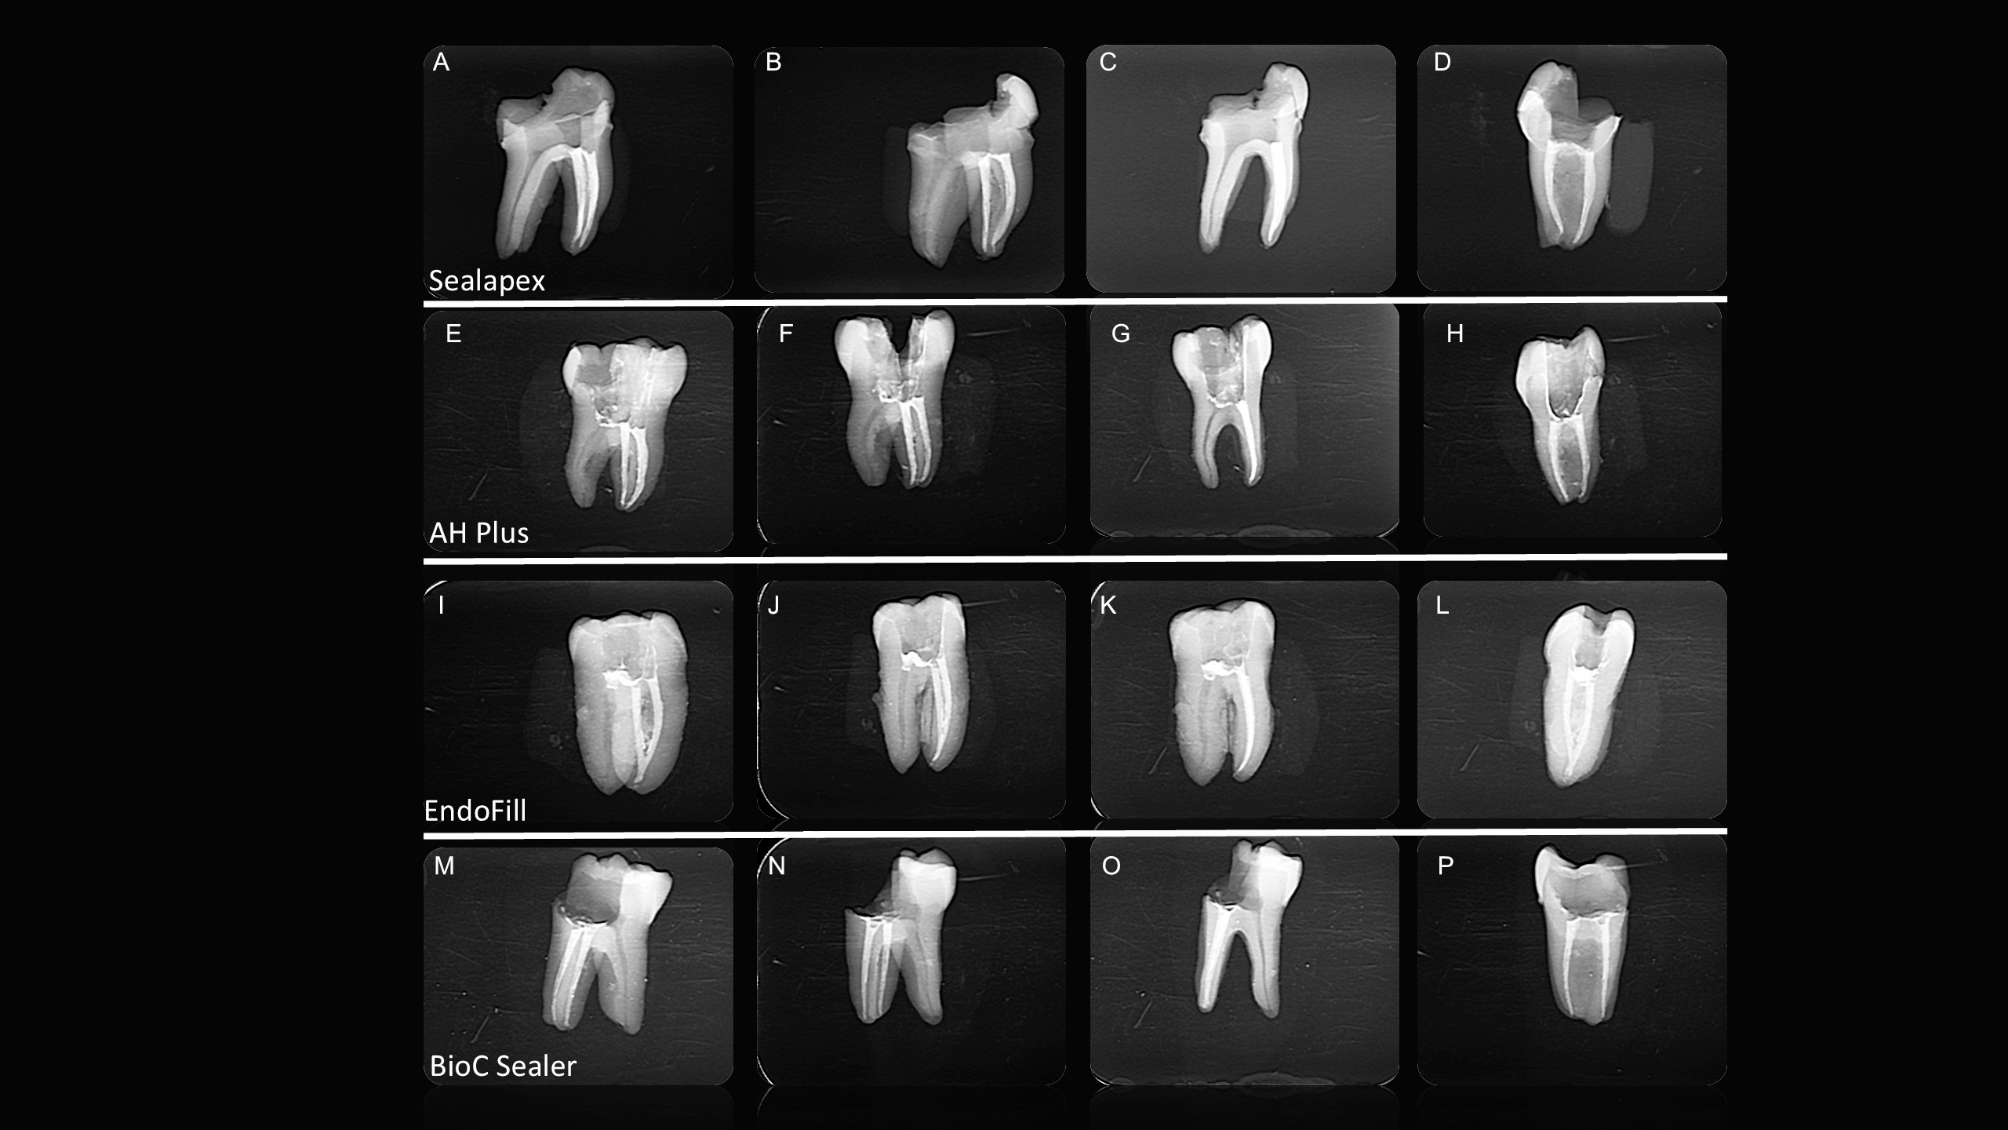

Fig. 2

(A-P). Periapical radiographs of endodontically treated teeth with different filling cements and separated instruments, acquired in distoradial, mesioradial, orthoradial, and proximal directions. All the images posed challenges for detecting the separated instrument.